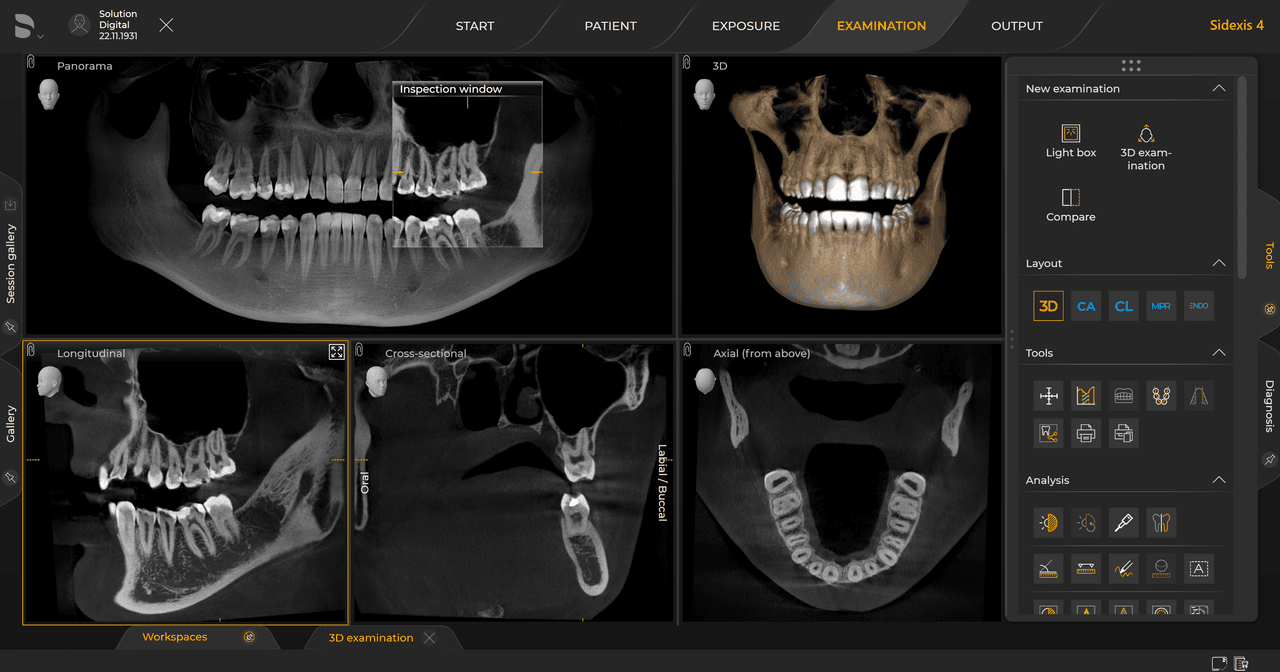

Las unidades de radiología de Dentsply Sirona funcionan exclusivamente con Sidexis 4. Sin embargo, la migración de datos de Sidexis XG a Sidexis 4 es muy fácil. Sidexis 4 permite una experiencia digital completa con las últimas herramientas